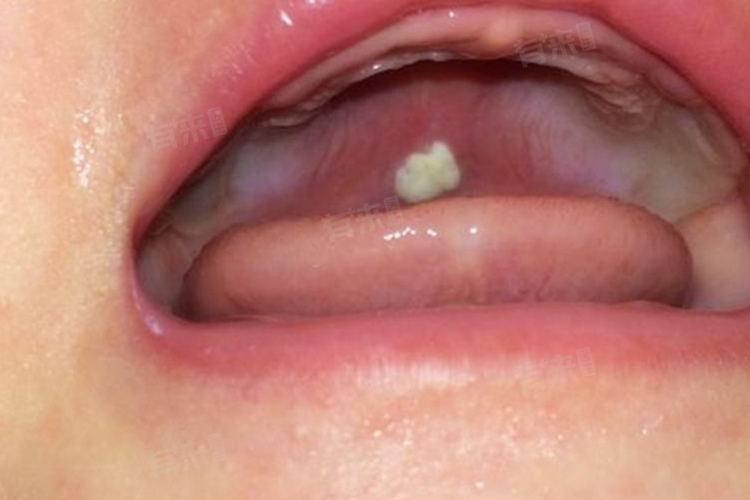

- 白色念珠菌感染的症状因感染部位不同而异,在口腔,感染可能表现为口腔白斑或鹅口疮,伴有味觉下降;在阴道,则可能引起霉菌性阴道炎,表现为白带增多、呈豆腐渣样,伴有外阴瘙痒、红肿等症状;白色念珠菌还可能引起呼吸道感染、胃肠道感染、泌尿系统感染等,具体症状包括发热、咳嗽、咳痰、吞咽困难、胸骨后疼痛、尿频、尿急等。